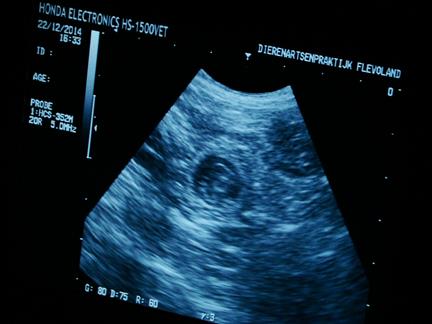

| 22 december 2014, eindelijk is het dan zo ver, 28 dagen na de dekking, dus tijd voor de echo om te kijken of Fleur drachtig is |

| na het scheren ligt Fleur braaf op haar rug, met onze dochter aan de ene kant en de assistente aan de andereke kant, en dan de eerste beelden, wat een mooi gezicht :-) |

niet alle foto's zijn even duidelijk |

| maar in de donkere ronde vlekken |

zie je witte lijntjes |

| en dat zijn .......... de puppies :-) |

ook zijn de hartjes al aan het kloppen, allemaal prachtig om te zien |